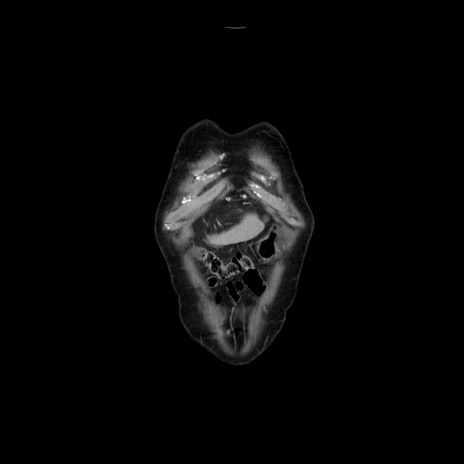

症例21(冠状断像)

【症例】70歳代男性

【主訴】腹痛

【現病歴】肝硬変・肝細胞癌にてかかりつけの方。約9時間前に食後より腹痛出現。症状が徐々に増悪し、嘔吐出現したため来院。

【既往歴】肝硬変、肝細胞癌(RFA、TACE後)